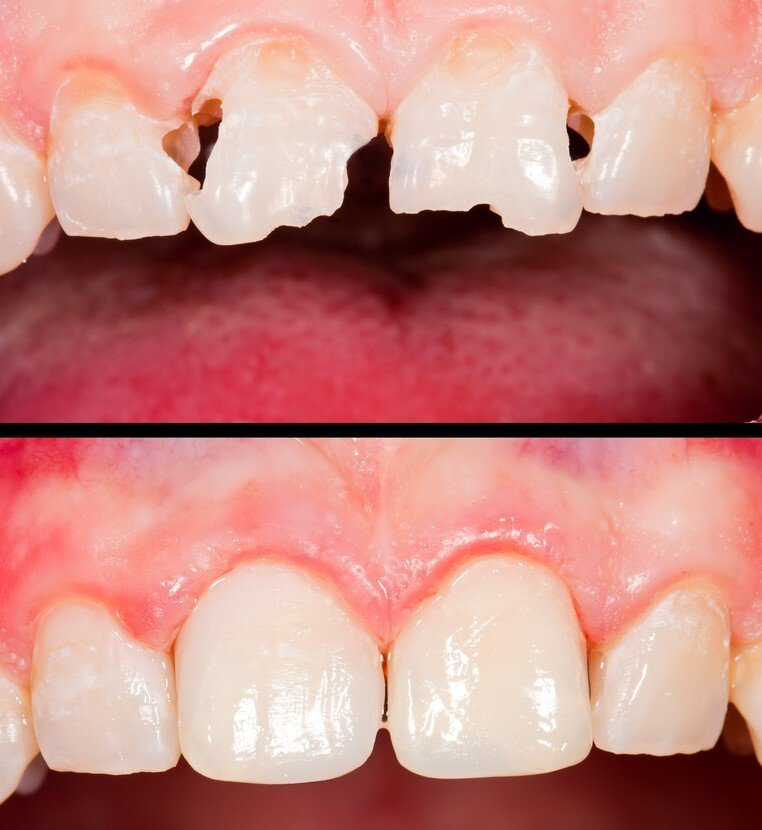

Restorative / Conservative Dentistry

As its name suggests, it tries to preserve by rebuilding teeth that have decayed or fractured, that have suffered trauma or are eroded; to preserve its function as a tooth.

Dental Aesthetics

The appearance of the teeth can be improved. The specialist team will evaluate each case to adopt the most appropriate technique: tooth whitening, composite restorations, ceramic veneers, metal-ceramic crowns, zirconium crowns, orthodontics, periodontal cosmetic surgery ...